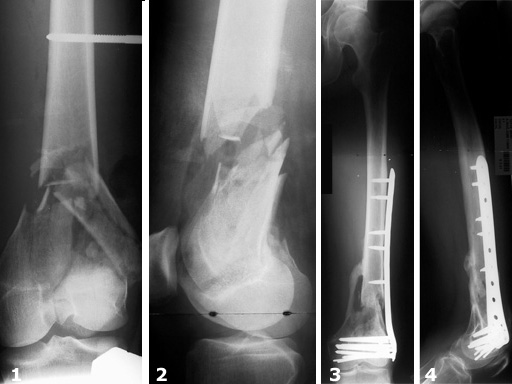

The LIS System Distal Femur (DF) is a new, fixed-angle implant system for the treatment of distal femoral fractures according to the principles of Minimally Invasive Surgery.

The criteria for inclusion were distal femoral shaft fractures and supracondylar and intraarticular femoral fractures of all degrees of severity. In this study, thirty-one distal femoral shaft fractures and eighty-five supracondylar and/or intraarticular femoral fractures were treated. There was a total of 45% (n=52) complex intraarticular fractures. With reference to the fractures treated, the follow-up rate was 93%. In 90% of the cases treated and followed up, fracture consolidation during the observation period could be confirmed.

Secondary cancellous bone grafting was only necessary in six cases. There were four cases of infection requiring surgical and antibiotic treatment. Implant loosening was observed in four cases, some of which could be attributed to technical errors during the operation. In contrast, secondary depressions during the course of healing were not observed at all.

The results of the study show that the new internal fixator is an excellent, safe procedure for the treatment of almost all fracture types, provided that thorough preoperative planning is performed and the surgeon has a sound knowledge of the operative technique. There is generally no need for primary cancellous bone grafting.